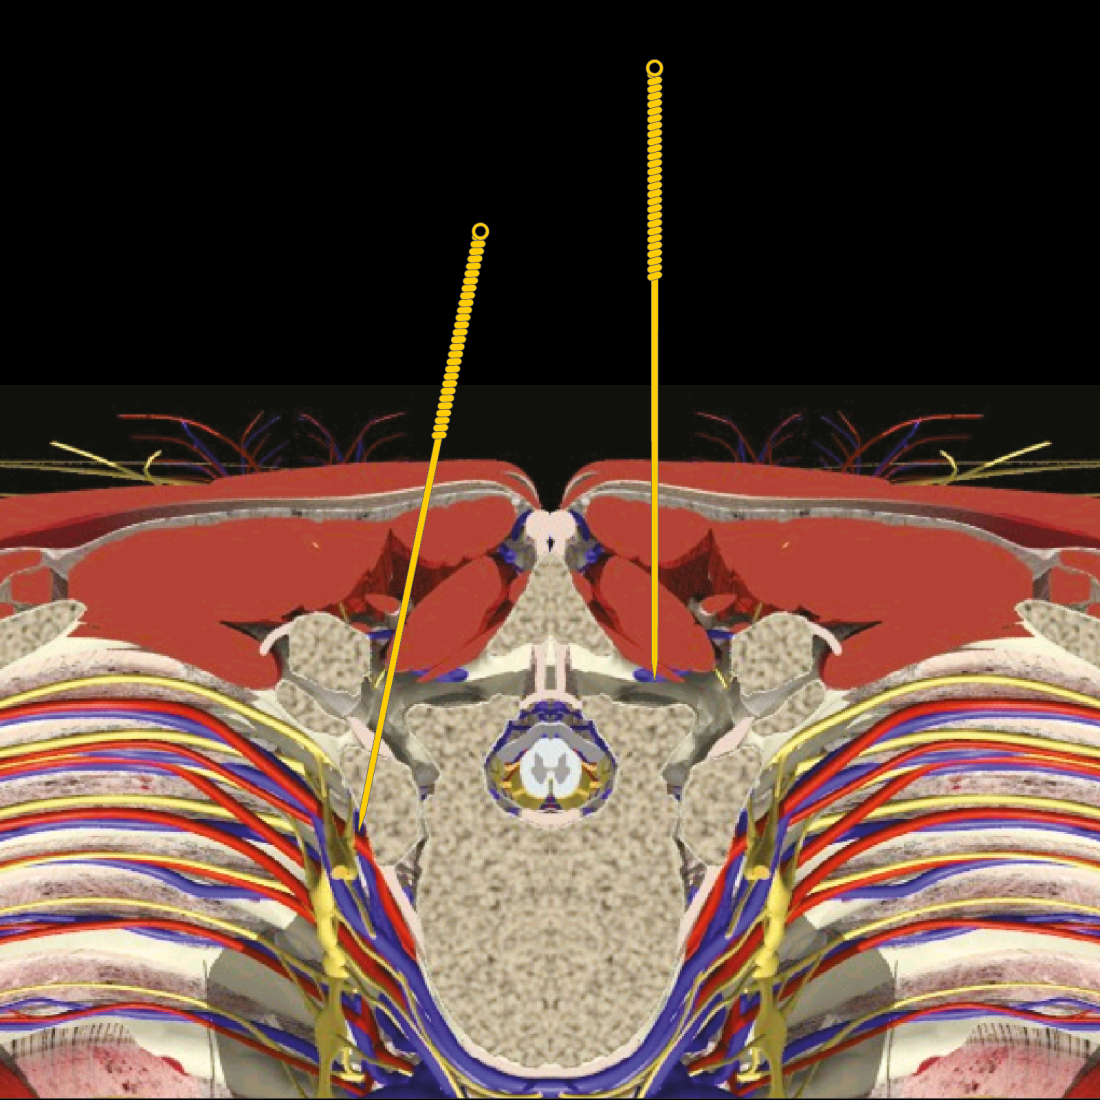

Acupuncture AE at Huatuojiaji

Stimulated by Jeong et al 2024.[1] Needling the multifidus muscle at one finger breadth from the midline. On the right side the needle aims correctly towards the lamina and on the left the lamina is missed. AE – adverse eventIF – impact factorKMD – Korean medical doctorCXR – chest x-ray (film)CT – computed tomography – … Continue reading Acupuncture AE at Huatuojiaji